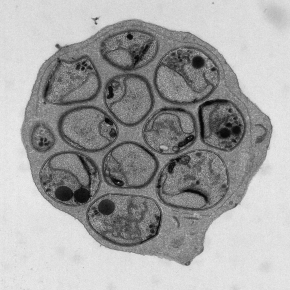

Face aux quelques 260 millions de cas de paludisme recensés chaque année, l’identification de nouveaux médicaments aux modes d’action innovants est une priorité. UA2239 est une molécule prometteuse qui élimine le parasite en bloquant de manière irréversible sa sortie du globule rouge. En supprimant le signal nécessaire à cette étape clé, elle empêche ainsi la multiplication du parasite et sa transmission au moustique. Publiée dans Science Advances, cette étude décrypte le mécanisme d’action de UA2239 et ouvre la voie au développement d’une nouvelle génération de traitements antipaludiques.